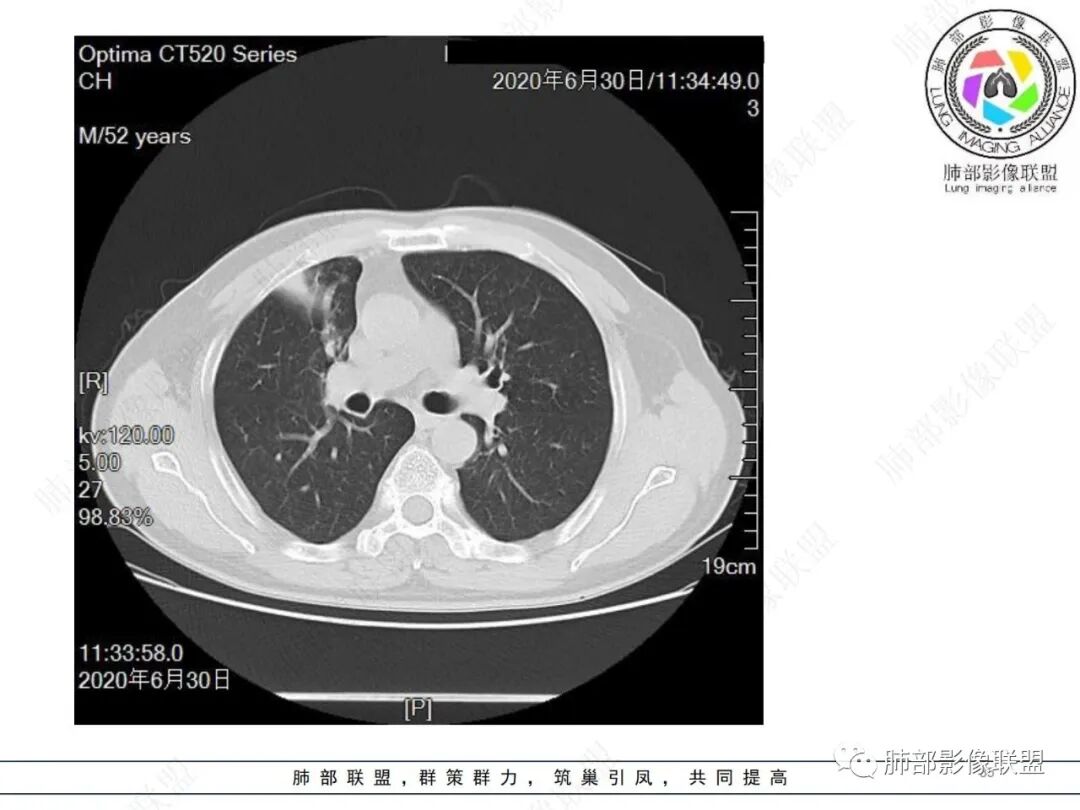

除了年龄,吸烟,湖泊样坏死符合鳞癌,其他都不符合,支气管截断,不在肿块中央,远处也没有明显阻塞样改变,更像爬行后截断,肿瘤标志物CEA高得厉害,其他鳞癌标志物并不高。这种坏死,低分化腺癌一样常见,强化远端也有强化,不符合鳞癌,所以我考虑低分化腺癌(伴或不伴有神经内分泌分化)或者肉瘤样癌。

借用傅老师标的图

边缘都是强化的肿瘤组织,鳞癌是不会这样的,符合腺癌

不符合鳞癌有四点:1,截断的支气管不在肿块中央,而是外朝内爬行(肿块外缘大于近端)2、支气管截断在前段,前段远端没有阻塞性改变。3、鳞癌是近端强化,远端为阻塞性的不强化粘液栓或明显强化的不张肺组织,这个是中间坏死,周围强化的肿瘤组织。4、肿瘤标志物CEA增高太明显,鳞癌标志物不高。